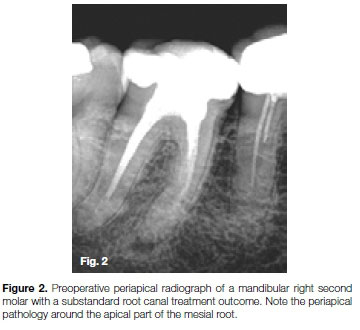

The tooth was anaesthetised and isolated before the previous obturation material was removed from the root canals using Endosolv E (Septodont) and a size 15 Hedstrom files. A size 10 K-File was introduced into the distal and mesio-buccal root canals, and it was possible to negotiate them to full working length. The same protocol was followed in the mesio-buc-cal root canal but it was impossible to negotiate the canal further. The tip of the instrument was hitting against a solid wall of dentin (Figure 3). A ledge formation in the canal was confirmed at the beginning of the root curvature.